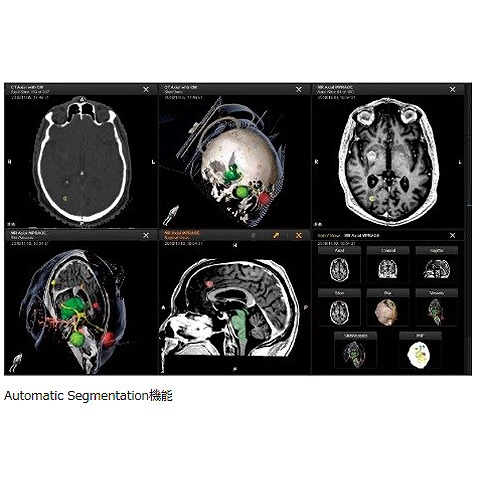

商品詳細ページ | メディカルブックセンター。放射線部|部門のご案内|洛和会音羽病院(京都市山科区)-救急。日本放射線治療専門放射線技師認定機構 [セミナー情報]。ご覧頂きありがとうございます。高精度放射線治療計画装置 Brainlab® Elements/iPlan®。\r\r「医療安全のための放射線治療計画装置の運用マニュアル : 受け入れ試験から日常管理まで」\r熊谷 孝三 / 日本放射線技術学会 / 日本放射線技師会 / 日本放射線治療専門技師認定機構\r定価: ¥ 4800\r\r【商品状態】\r特筆する痛み・折れなどはありません。インテンシヴィスト 6冊セット。\r中は問題なく読める状態です。胃拡大内視鏡。\rマーカー記入はありません。BLS ガイドライン 一次救命処置 プロバイダーマニュアル AHAガイドライン。\rタバコ、ペットなしの部屋で保管していました。2021年度 セルフトレーニング問題。\r確認を行いましたが、その他の書き込み等の見落としがあるかもしれませんご了承の上、ご購入下さい。BLSブロパイダーマニュアル2020。\r\r【発送に関して】\r送料無料の匿名配送で対応致します。「仙人瞑想法」 高藤聡一郎。\r\r【注意事項】\r個人保管の中古品です。《18日まで値下げ》臨床経穴学。\r使用感は人によって感じ方に差があります。(日本語版) 新品・未開封 大天使ラファエルオラクルカード(2020年 改定版)。\r神経質な方のご購入はお控え下さい。横山式筋二点療法 疾患別圧痛点の痛みを消す反射筋一覧図表集。\r購入後のクレームは対応しかねます。医療の資格 診療情報管理士2022 模試4回分 基礎分野・専門分野。\r上記をご理解頂ける方のご購入をお願いします。【裁断済】心臓血管外科手術 虎の巻。\r\r【その他】\r喫煙者&ペットはなしの環境で管理しています。5年でマスター消化器標準手術 消化器外科専門医への道。\r商品撮影は昼夜問わず白色電灯下で行います。活力増進 強圧微動術。\r\r#熊谷孝三 #熊谷_孝三 #日本放射線技術学会 #日本放射線技師会 #日本放射線治療専門技師認定機構 #本 #自然/医療・薬学・健康